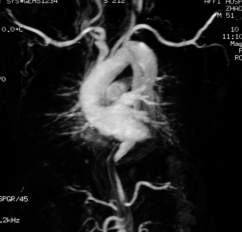

工作室以“健康中国2030”健康服务体系建设为指导,坚持创新驱动发展,依托高层次人才优势,凝聚合力,增强创新能力,提升战斗力。围绕大健康产业,紧盯医疗行业发展要求,积极开展新技术临床研究、技术技能培训推广、学术交流、业务指导和成果转化,围绕职业教育类型教育特征,紧盯培养技术技能人才要求,深入开展“三教”改革与“三全”育人体系建设,坚持研究成果服务临床医疗行业发展,提升诊疗能力和水平,提高服务质量,践行绿色医疗;坚持研究成果服务专业发展,培养学生发展能力,提升学生技术技能水平;坚持“三教”改革实践、课程思政体系研究与构建,职业精神凝练与培养,深化“医教一体、学教实岗”、虚实融通、三阶梯分层递进的人才培养,稳步提升培养质量,增强核心竞争力,推动学院高质量发展。